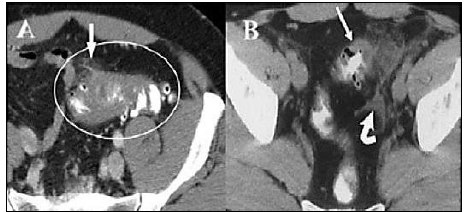

“Mulher, 52 anos, comparece ao pronto-socorro com dor em fossa ilíaca esquerda há 1 dia, de caráter progressivo, mas de média intensidade. Ao exame, descompressão-brusco dolorosa postiva. Apresenta o seguinte achado de TC sem contraste”.

Trata-se, provavelmente, de